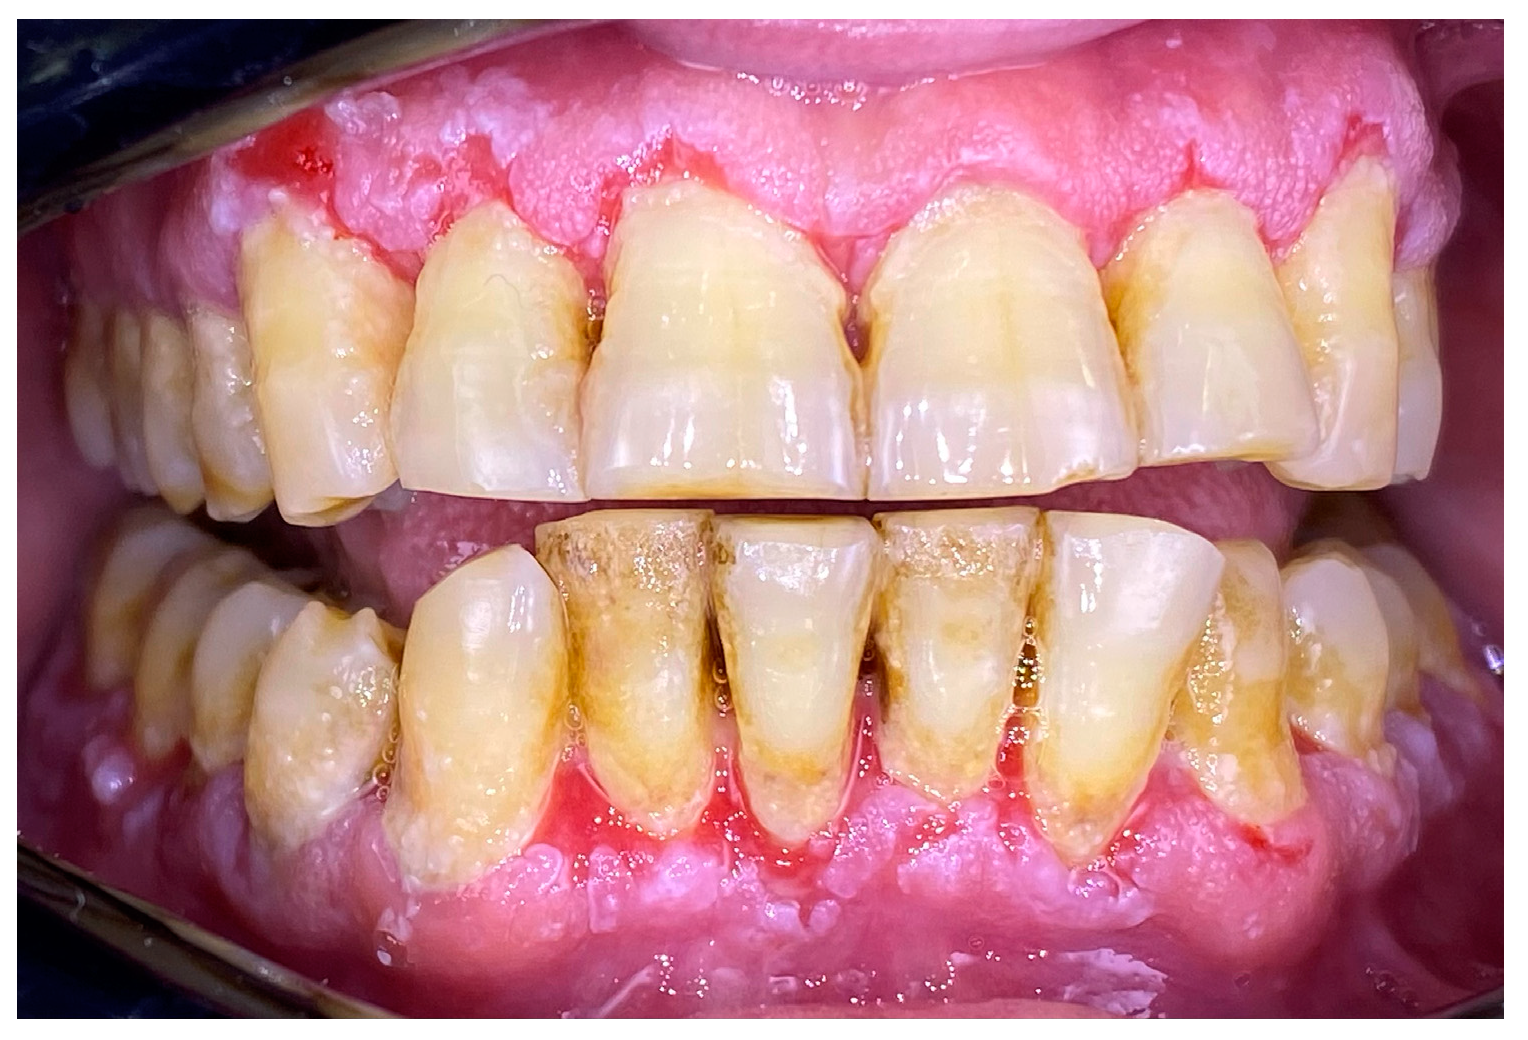

2.1. Clinical Case 1—Mucous Membrane Pemphigoid (MMP)

2.2. Clinical Case 2—Pemphigus Vulgaris (PV)

2.3. Clinical Case 3—Oral Lichen Planus (OLP)